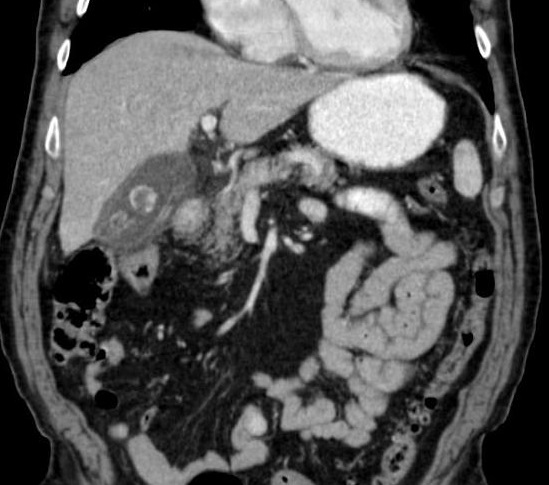

Image une cholecystite

aigue avec vesicule distendue , paroi vesiculaire

est tres epais et images de oedemes de la sous

sereuse . Coupe TDM axiale a contrast

intraveineuse |

Meme cas en coupe frontale (

coronal ) . Images de oedeme sous sereuse et

epanchement perivesiculaire et canal cystique est en

vue nette |